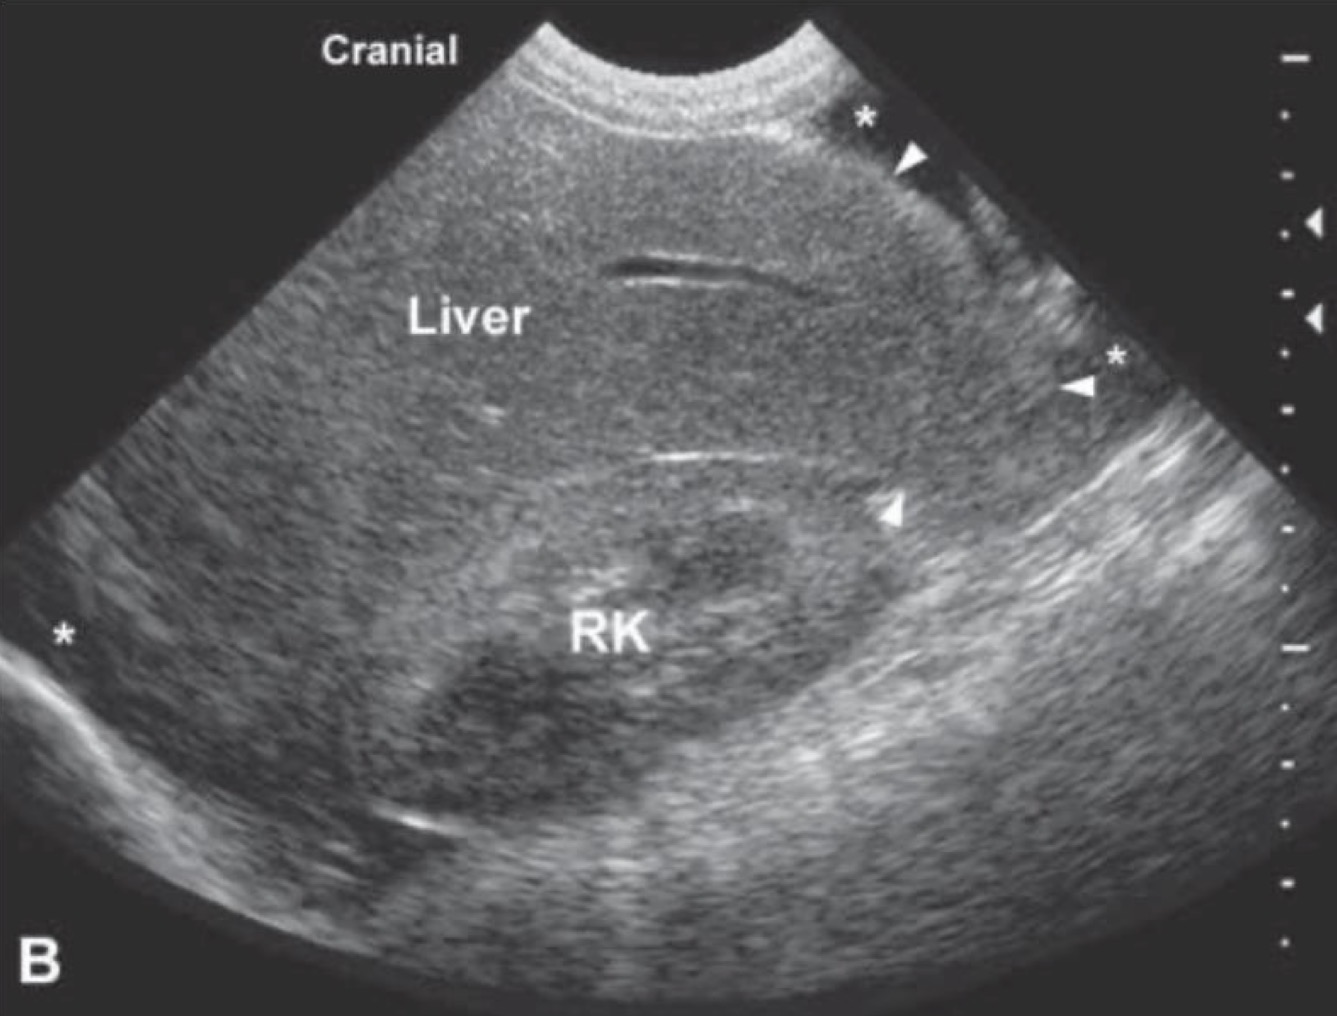

Hepatomegaly

What is occurring in this patient?